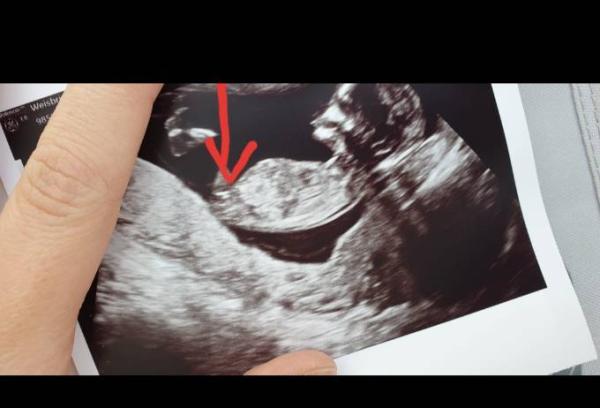

Ich hatte dir eigentlich eine Mail geschickt ..ist die nicht angekommen? Also, das Bild ist von meinem Sohn aus 12+2 ..der Zipfel ist für mich eindeutig mittlerweile..das Bild ist im Prinzip vob unten aufgenommen, ich hoffe ihr erkennt es..

Bild zu